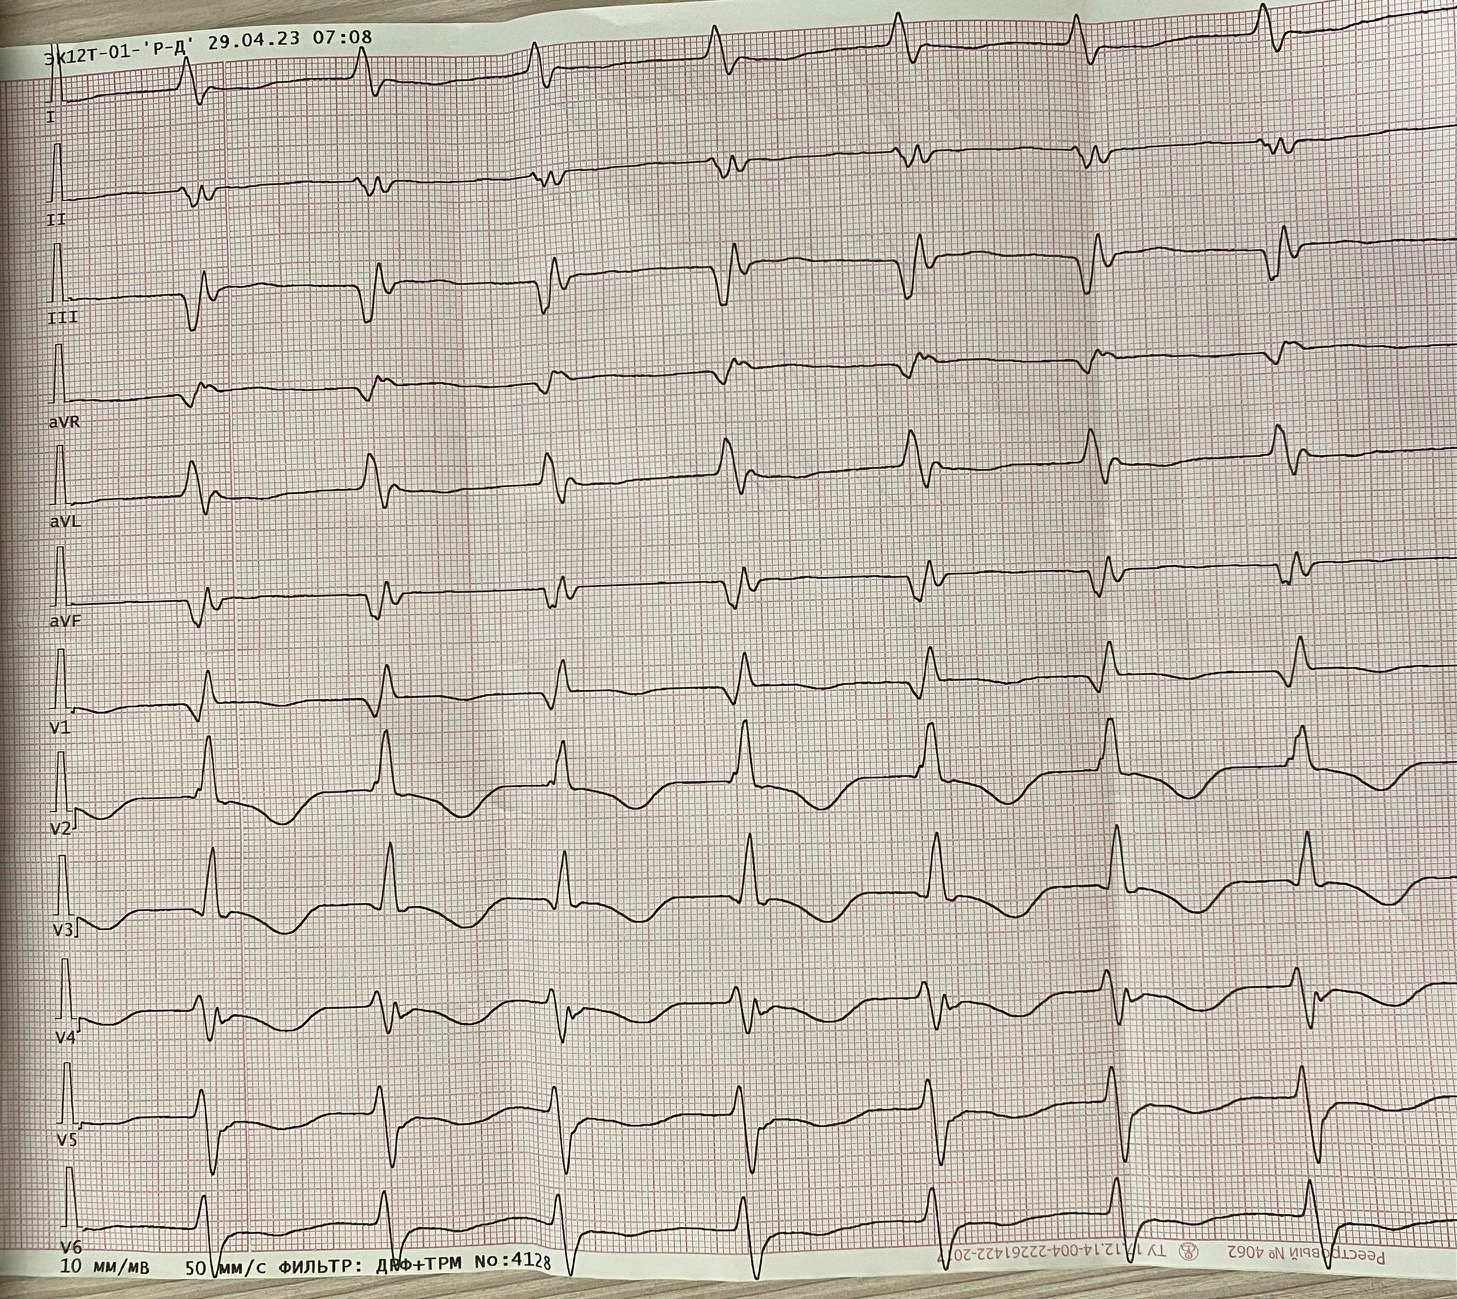

Ускоренный узловой

Обсуждалось здесь https://vk.com/club84409679?w=wall-84409679_13555%2Fall